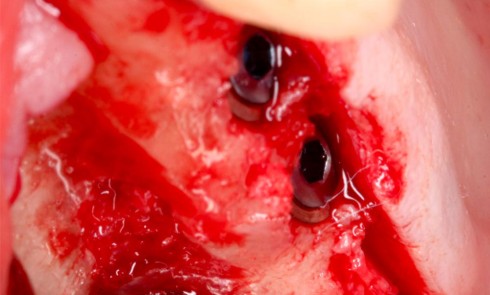

Adolescente de 17 ans ayant trois dents (12, 11, 21) expulsées lors de travaux aux champs (fig. 5), ainsi qu’une luxation latérale de la 13. Elle est adressée par les urgences du CHU de Rennes et la consultation a lieu 6 heures…